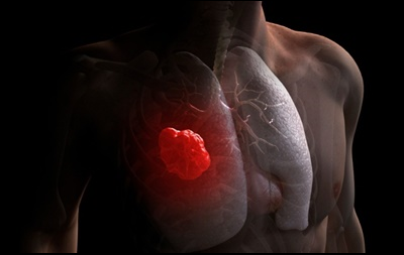

이번 기사에서는 폐암 초기 증상에 대해 자세히 정리해 알려 드리겠습니다 . 폐암은 국내암 사망률 1 위로, 과거에는 흡연이 폐암의 주된 원인 이었지만 , 현재는 비흡연 폐암 환자도 대폭 증가했습니다 . 폐암은 의학 기술로 발달하여 생존율이 높아지고 있습니다 . 폐암의 초기 증상은 무엇인가를 알아보겠습니다.

폐암의 초기 증상